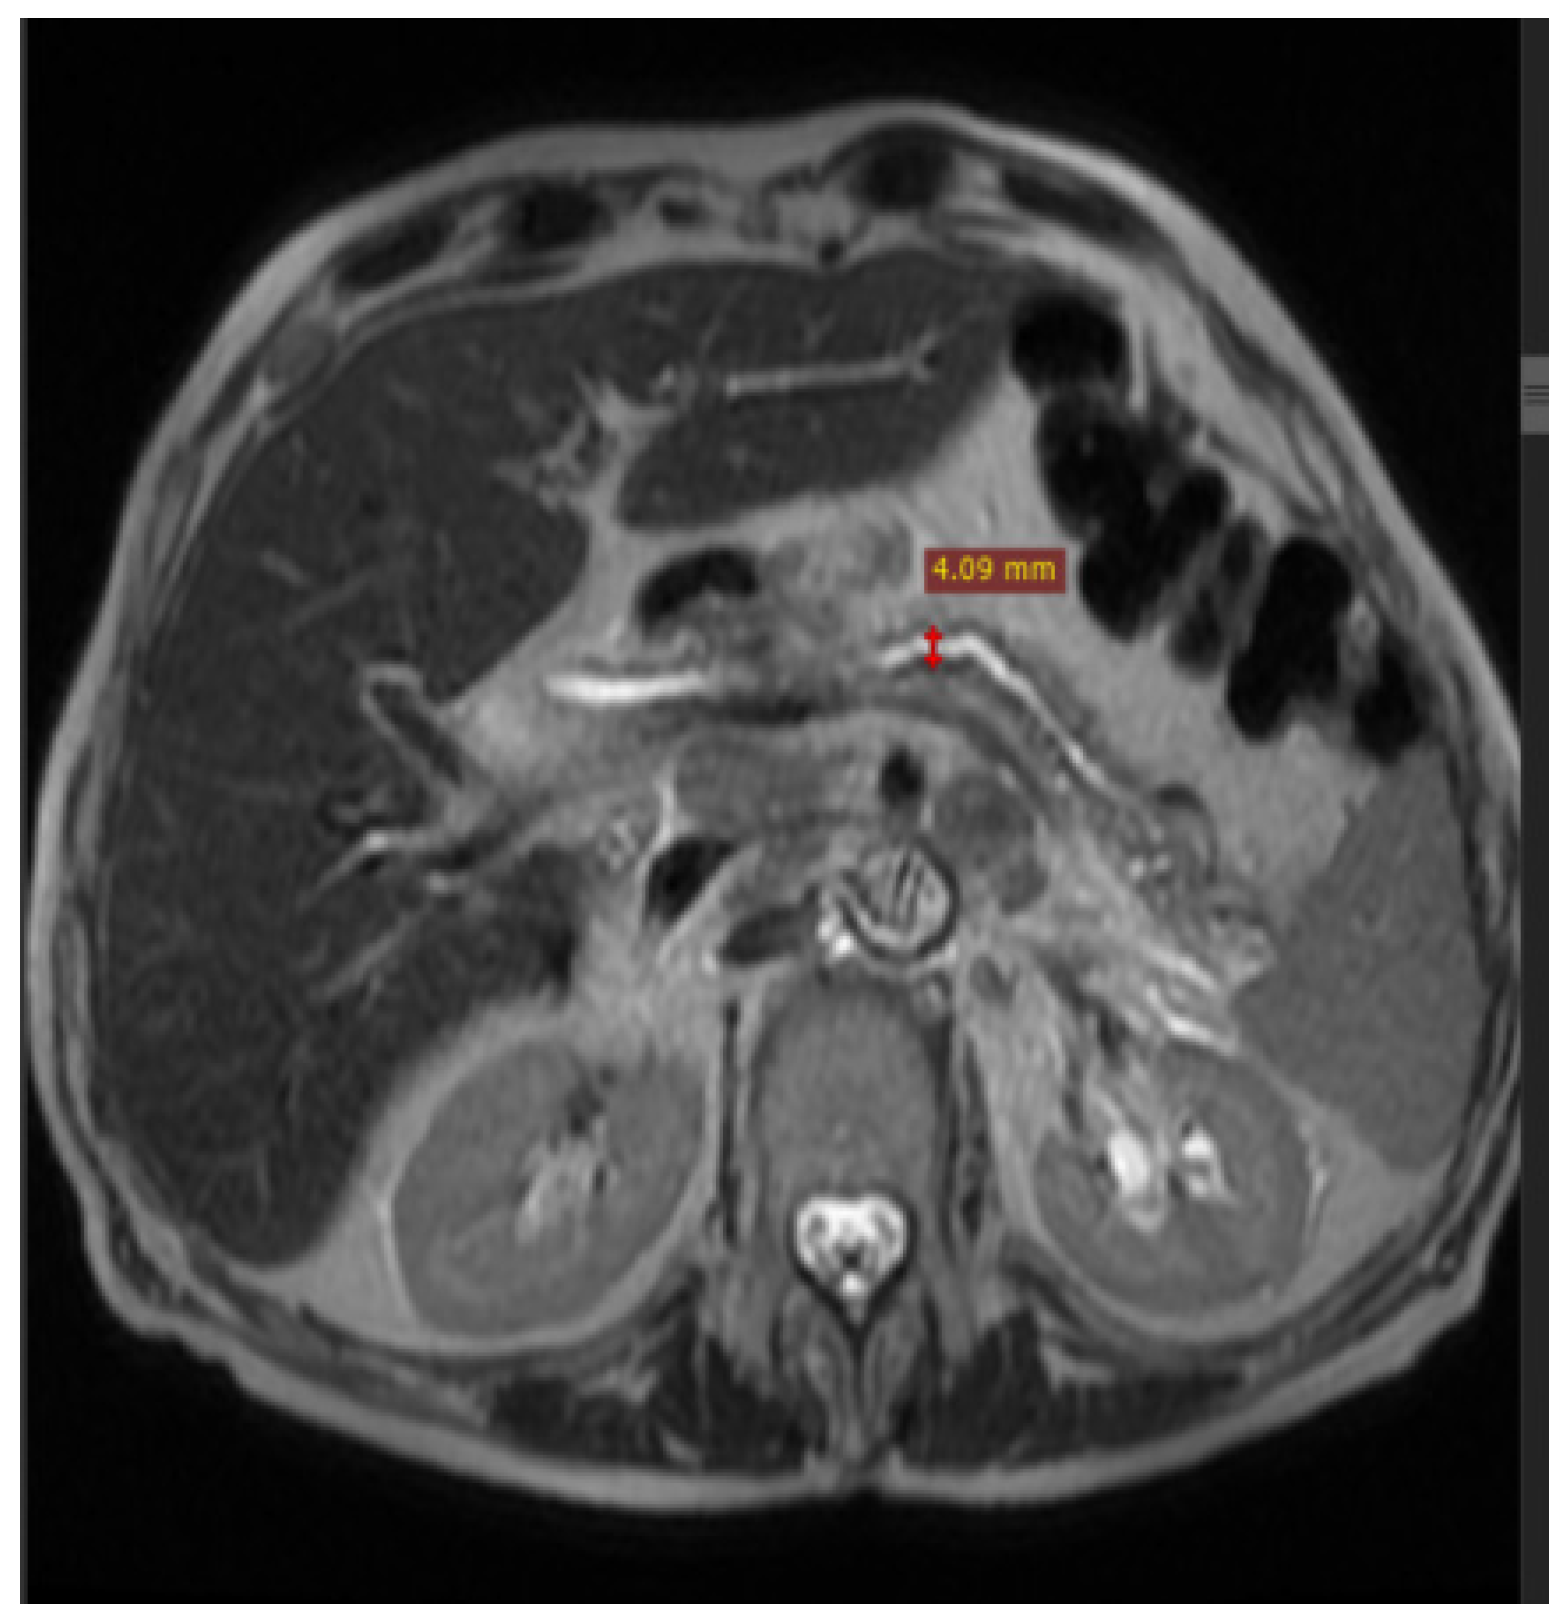

2. Case Report